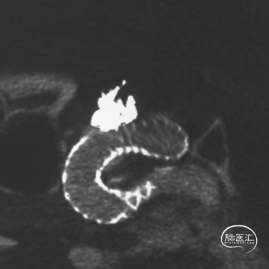

动脉瘤相对窄颈,拟先行弹簧填塞后行Surpass Evolve血流导向装置植入。

SL-10塑形后填入Target 16/50,14/50两枚弹簧圈。

动脉瘤大部栓塞,瘤颈部造影剂滞留。

Vaso CT重建 支架打开、贴壁良好。